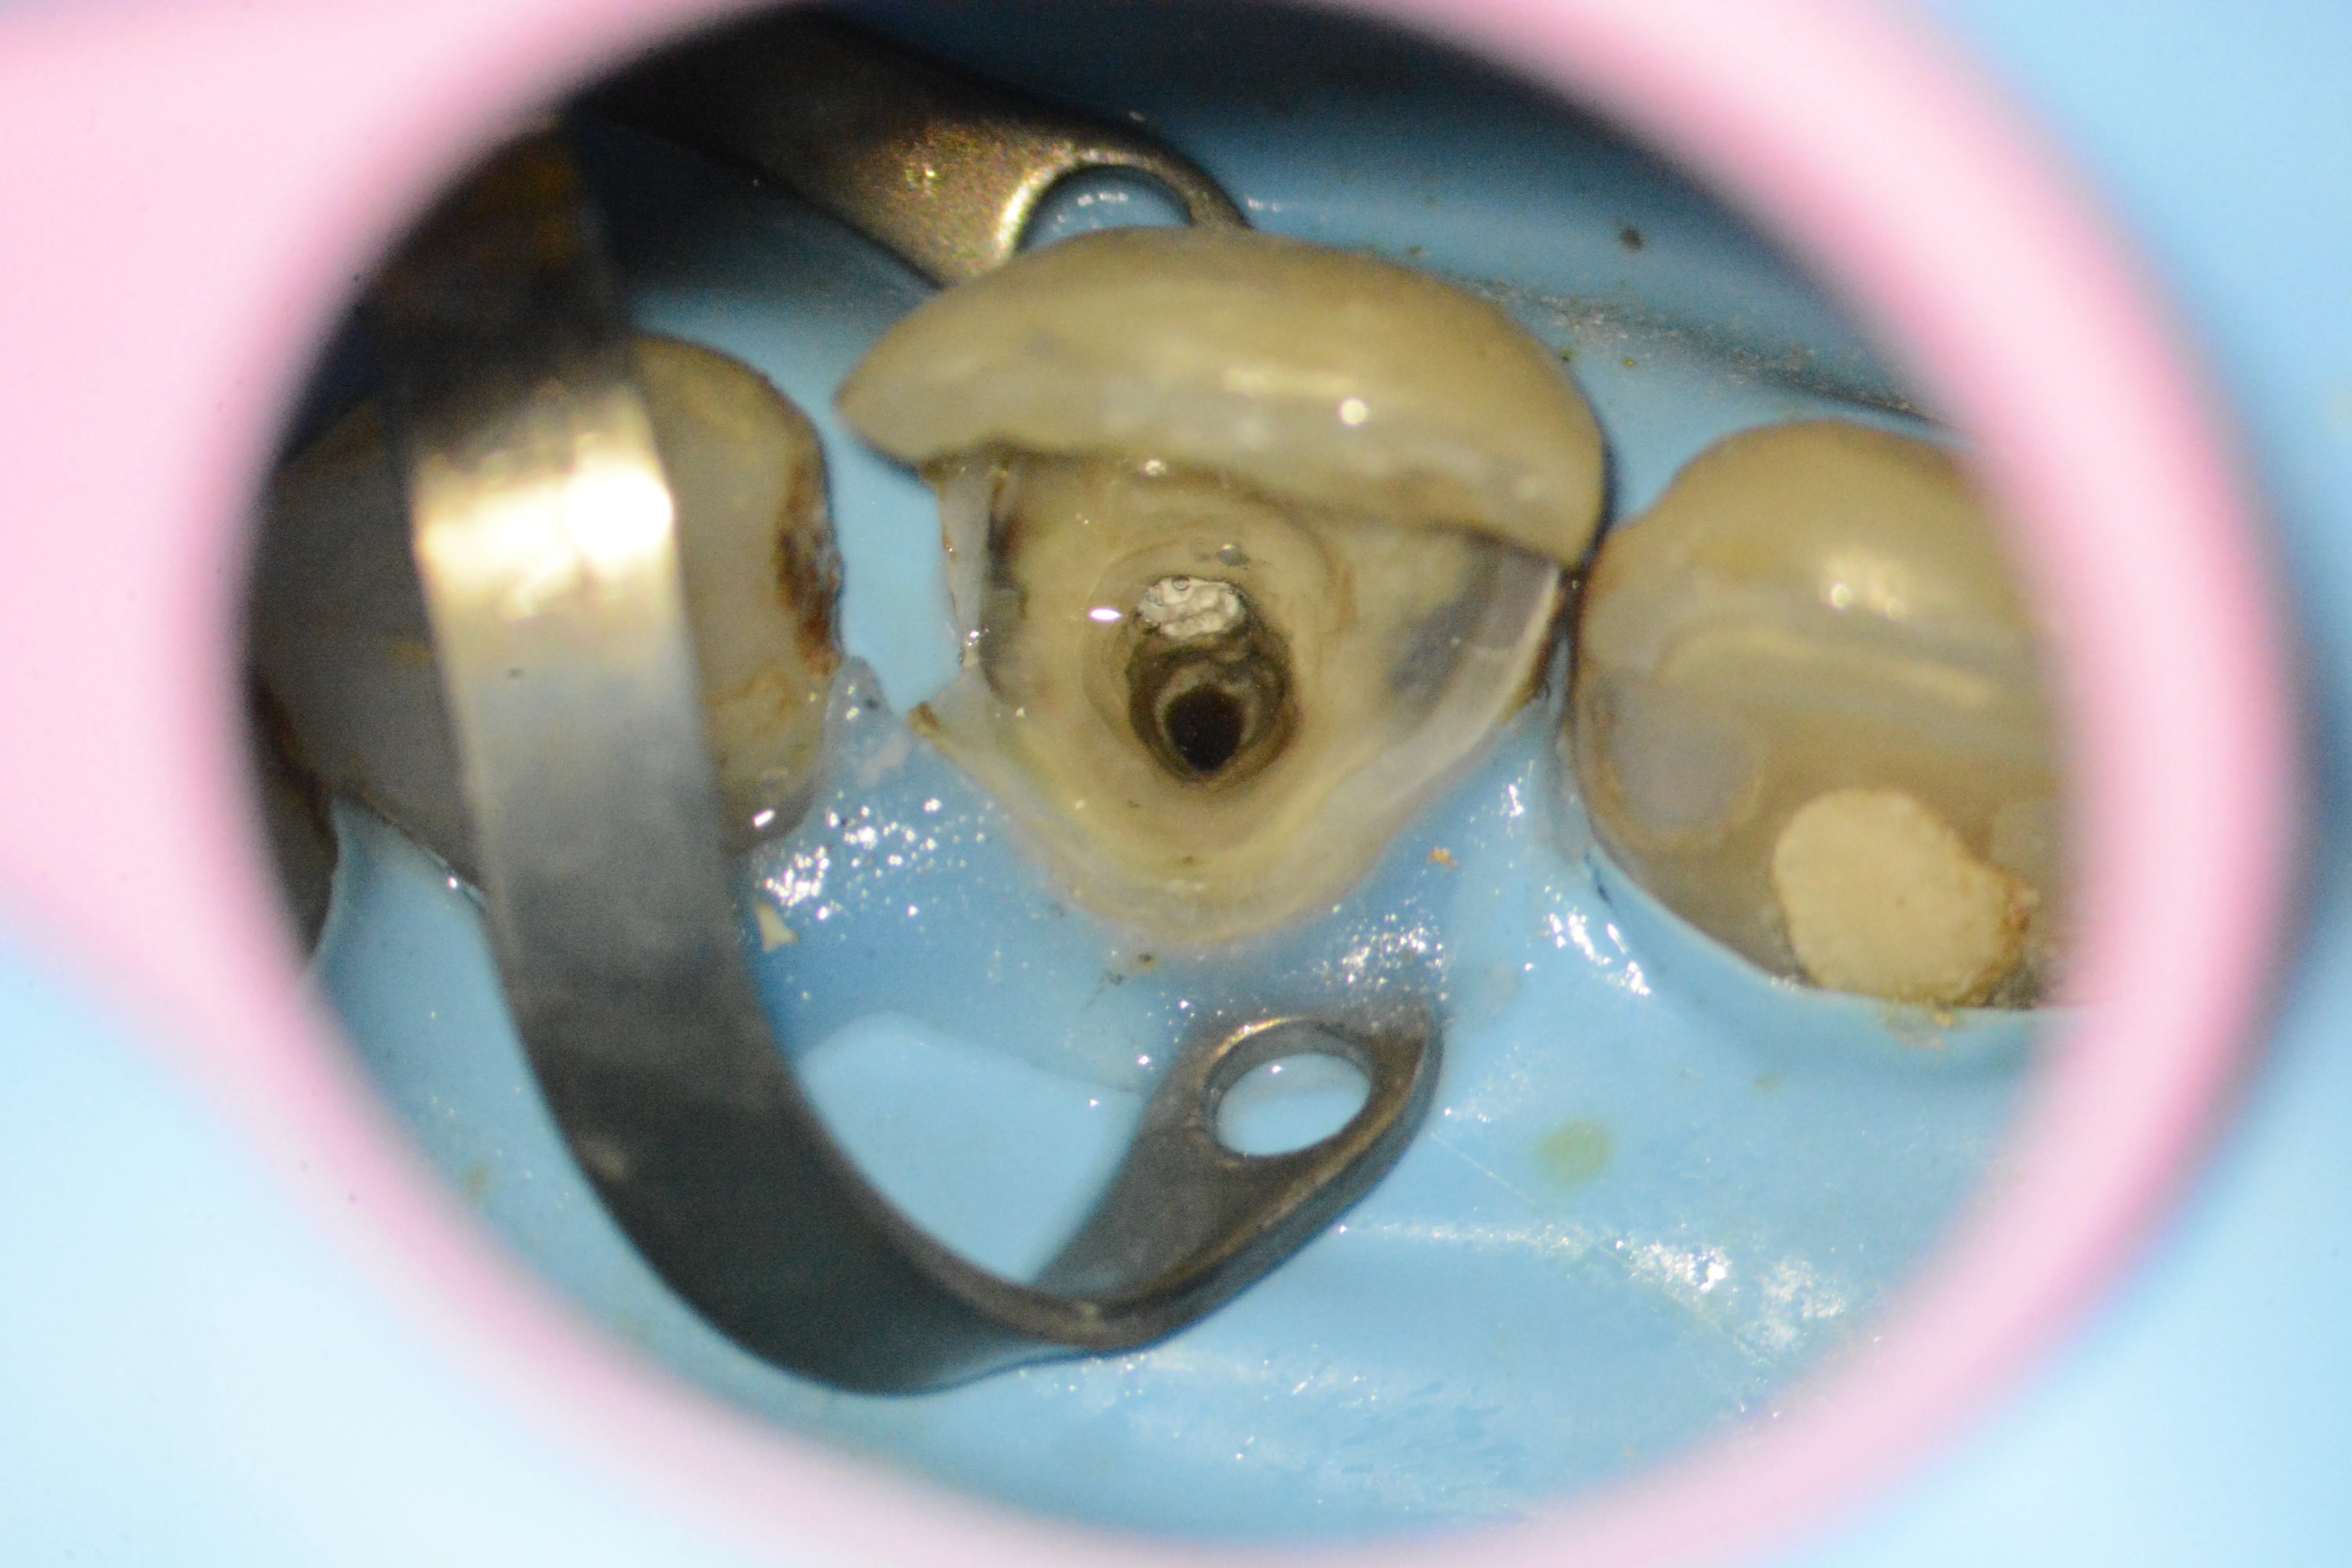

6 – Aspectul frezei din canalul radicular

7 – Expunerea frezei pentru a încerca mobilizarea ei